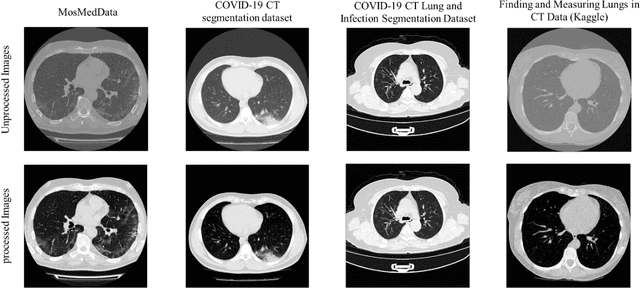

Abstract:Since the breakout of coronavirus disease (COVID-19), the computer-aided diagnosis has become a necessity to prevent the spread of the virus. Detecting COVID-19 at an early stage is essential to reduce the mortality risk of the patients. In this study, a cascaded system is proposed to segment the lung, detect, localize, and quantify COVID-19 infections from computed tomography (CT) images Furthermore, the system classifies the severity of COVID-19 as mild, moderate, severe, or critical based on the percentage of infected lungs. An extensive set of experiments were performed using state-of-the-art deep Encoder-Decoder Convolutional Neural Networks (ED-CNNs), UNet, and Feature Pyramid Network (FPN), with different backbone (encoder) structures using the variants of DenseNet and ResNet. The conducted experiments showed the best performance for lung region segmentation with Dice Similarity Coefficient (DSC) of 97.19% and Intersection over Union (IoU) of 95.10% using U-Net model with the DenseNet 161 encoder. Furthermore, the proposed system achieved an elegant performance for COVID-19 infection segmentation with a DSC of 94.13% and IoU of 91.85% using the FPN model with the DenseNet201 encoder. The achieved performance is significantly superior to previous methods for COVID-19 lesion localization. Besides, the proposed system can reliably localize infection of various shapes and sizes, especially small infection regions, which are rarely considered in recent studies. Moreover, the proposed system achieved high COVID-19 detection performance with 99.64% sensitivity and 98.72% specificity. Finally, the system was able to discriminate between different severity levels of COVID-19 infection over a dataset of 1,110 subjects with sensitivity values of 98.3%, 71.2%, 77.8%, and 100% for mild, moderate, severe, and critical infections, respectively.